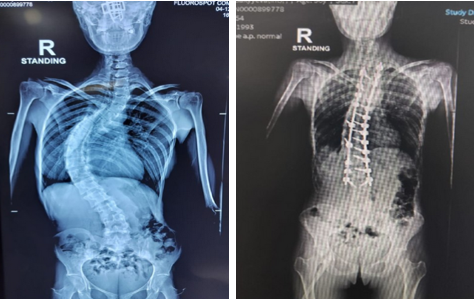

Spinal Deformity Correction (Scoliosis and Kyphosis)

Correcting abnormal spinal curvatures for better alignment and function.

Surgery to straighten and stabilize an abnormally curved spine using rods, screws, and fusion.

Curves are corrected with rods and screws. The bones are fused to maintain correction permanently.

- Straighter spine and improved appearance